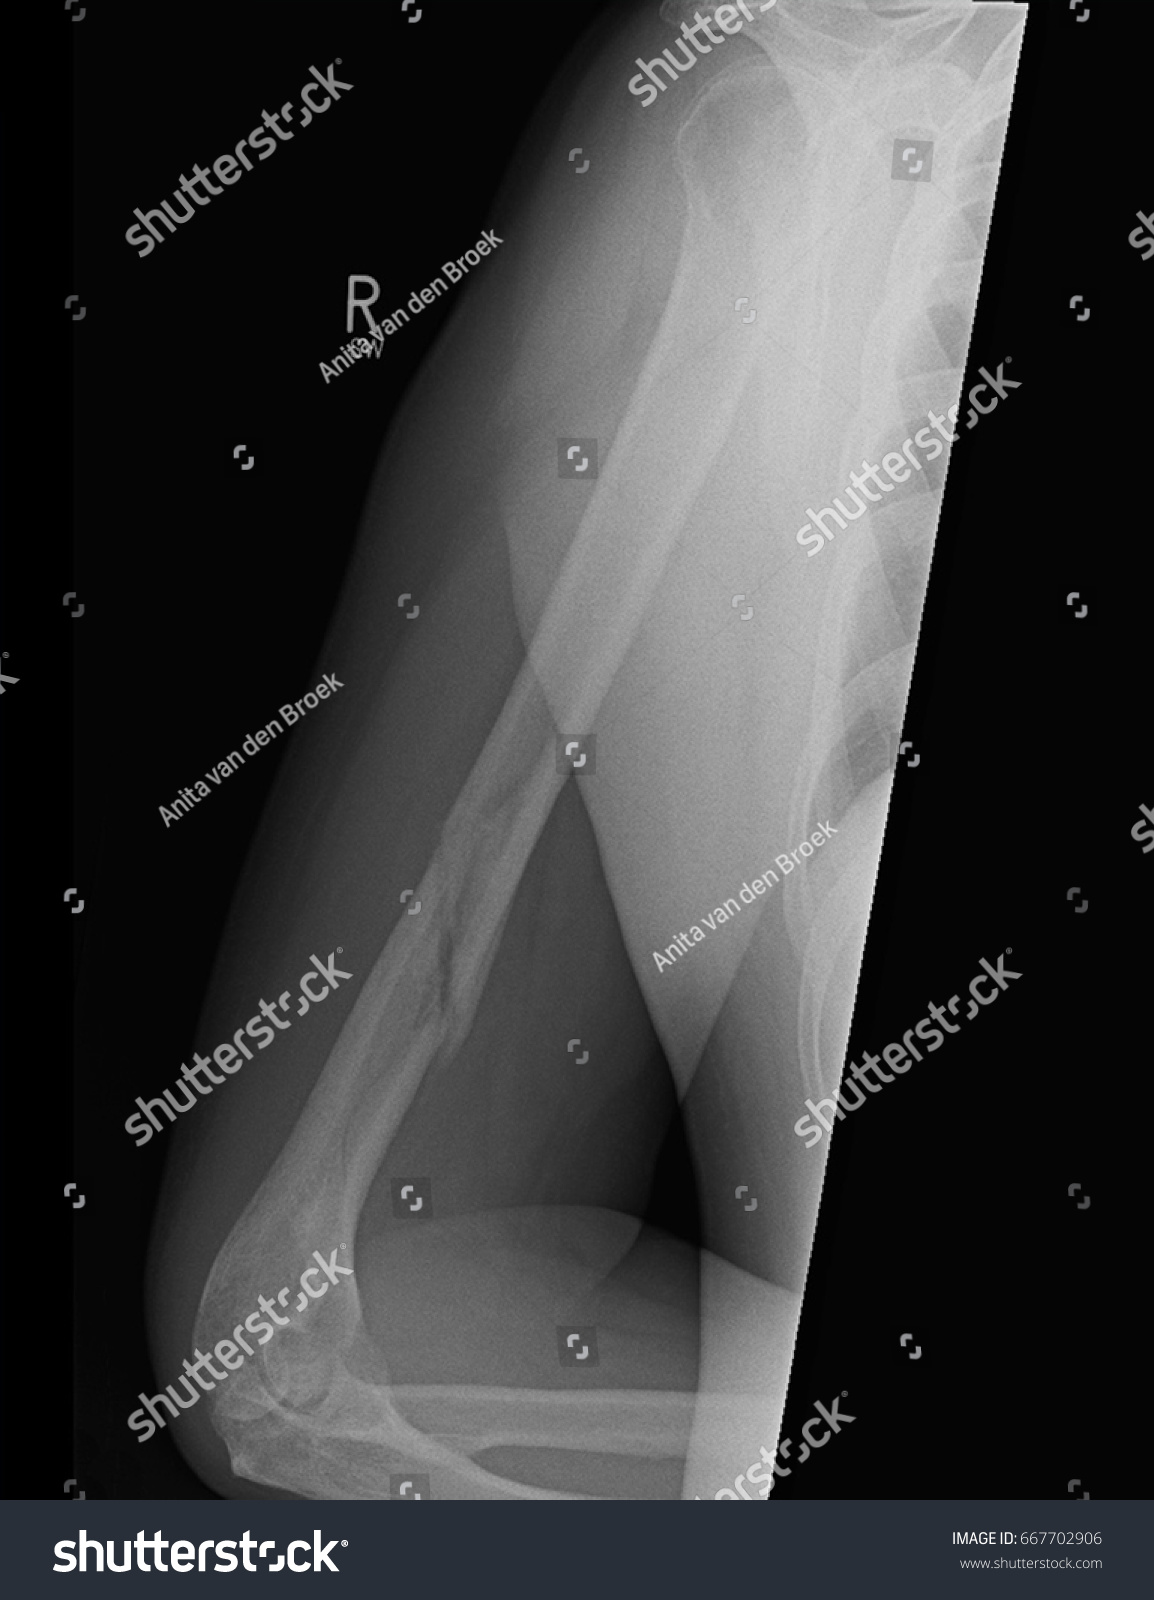

Broken Humerus Xray Showing Compound Spiral Stock Photo 667702906 Spiral Humerus Break nonoperative treatment works well with the aid of ligamentotaxis in most humeral shaft fractures without significant initial. Spiral fractures typically affect long bones (those that are longer than they are wide) found in your arms, legs, hands, and feet. You develop it in the shaft of the humerus when you. — a spiral fracture is a broken bone. Spiral Humerus Break.

Broken Humerus Xray Showing Compound Spiral Stock Photo 666295192 Spiral Humerus Break — a spiral fracture is a bone fracture that occurs when a long bone is broken by a twisting force. Trauma from a fall or accident are often the cause of this type of fracture. Spiral fractures typically affect long bones (those that are longer than they are wide) found in your arms, legs, hands, and feet. a. Spiral Humerus Break.

Broken Humerus Xray Showing Compound Spiral Stock Photo 667702792 Spiral Humerus Break there are two types of humerus fractures based on the location of the break (s). Treatment can depend on the severity of the. You develop it in the shaft of the humerus when you. Spiral fractures typically affect long bones (those that are longer than they are wide) found in your arms, legs, hands, and feet. nonoperative treatment. Spiral Humerus Break.